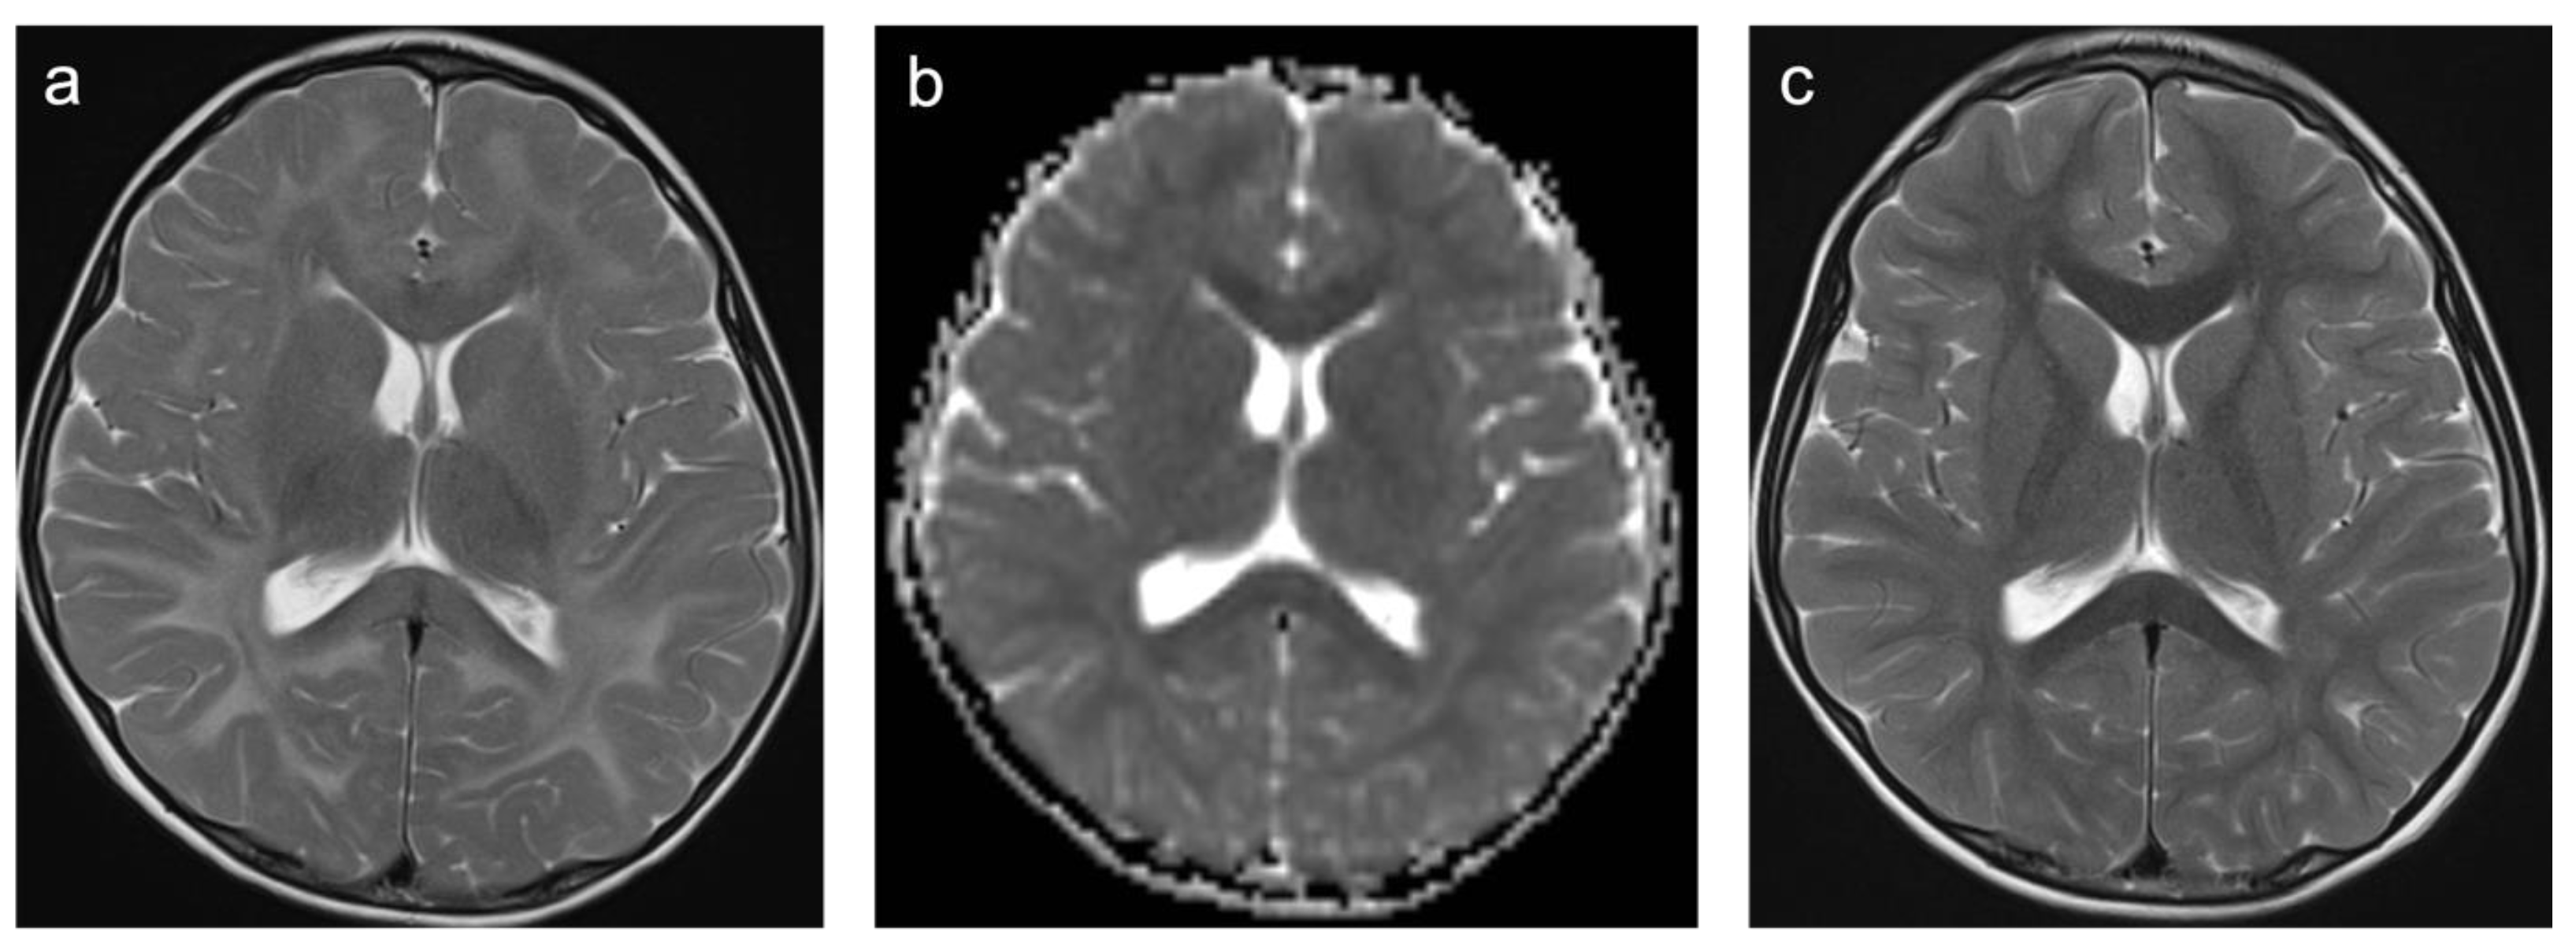

Group 2 consisted of 30 patients. Eight patients (27%) suffered from perinatal asphyxia; one of them was born preterm. Ten patients (33%) were diagnosed with periventricular leukomalacia (PVL); six of them were born preterm and two had co-occurring intraventricular hemorrhage (IVH). Ten patients (33%) showed signs of ischemic stroke. Eight of these strokes were of obscure or of unknown origin (cryptogenic). One was suspected to be cardio-embolic in a patient with a congenital heart disease with a ventricular septal defect in inherited Xq24 microdeletion syndrome and one as associated with sickle cell disease. The remaining two patients (7%) suffered from a cerebral venous sinus thrombosis with venous outflow obstruction leading to ischemia. A representative case is shown in Figure 4. In total, 60% of patients were female and the mean age was 7.8 years (min 3 days; max 18.4 years). A total of 57% of patients were examined with contrast-enhanced MRI and 12% of those examinations showed at least one enhancing lesion. WMSAs in this group of patients were localized supratentorial only. A total of 43% of patients had multifocal WMSAs.

Figure 4. Representative case “Non-genetic hypoxic and ischemic insults”: term-birth asphyxia. DWI/ADC (a,b), T2W (ce), FLAIR (f) sequences. Neonatal resuscitation after severe term-birth (40 weeks) asphyxia in a three-day-old girl. (ac). Treatment with therapeutic hypothermia. MRI shows predominantly white matter injury as one of the patterns identified in term-birth asphyxia [20]. The same girl examined again at the age of four years (df). MRI shows periventricular signal hyperintensities in T2W/FLAIR sequences.